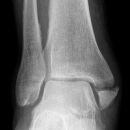

Maisonneuve

Spiralfraktur Tibia